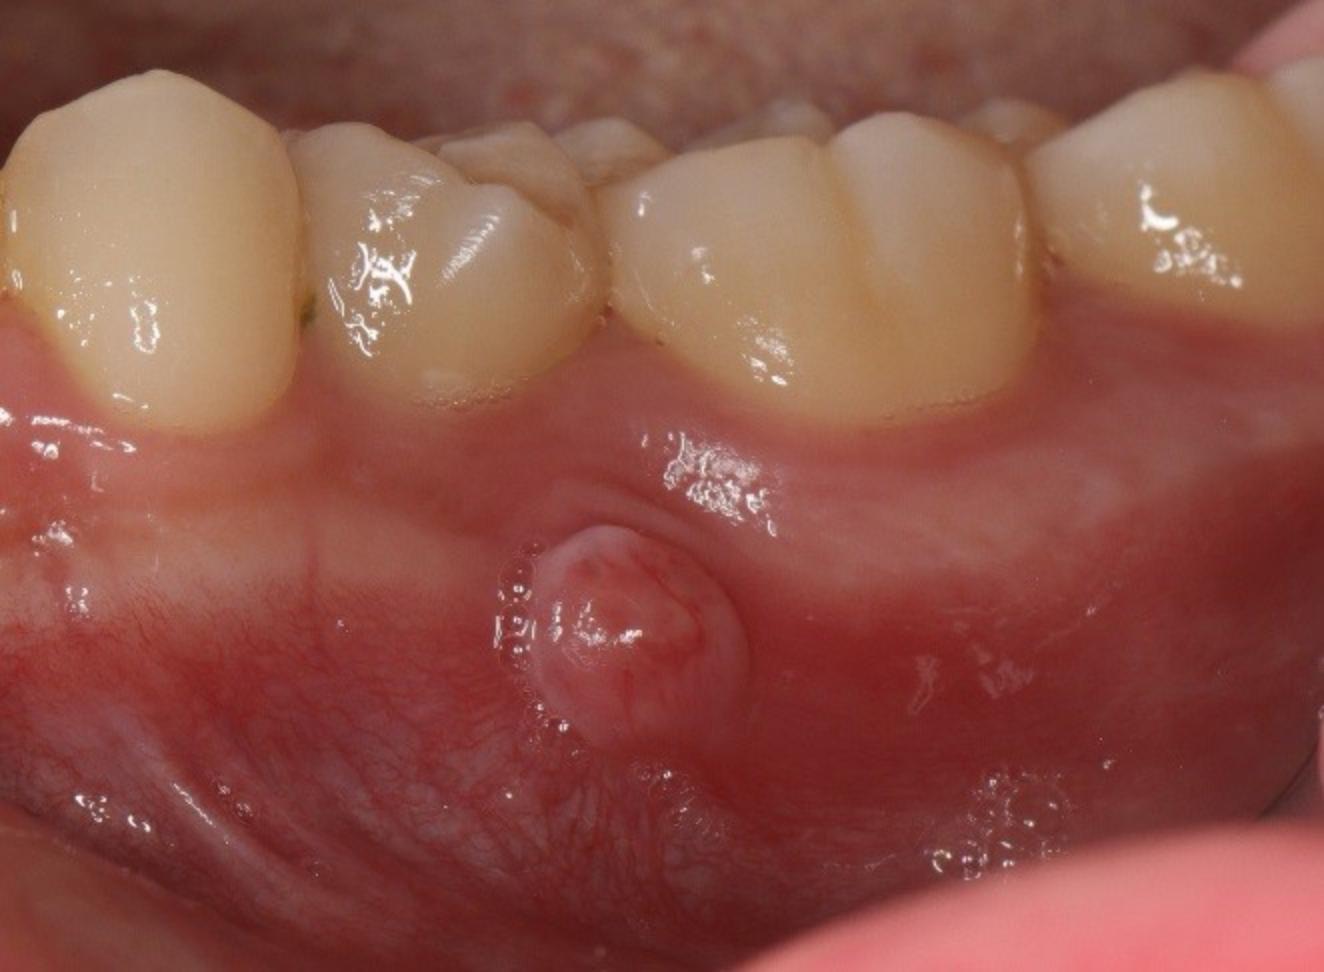

牙齦膿包示意圖(圖片來源/新光醫院)

一旦確認是牙髓來源的,一般常見的原因是根尖周圍發炎或膿腫,經由竇管在牙齦產生一個膿液排出的開口,這是一種壓力得以宣洩的方式。在這種情況下如果牙齒剩餘齒質仍足夠並且有一定的成功率和預後時,會建議進行患病牙的根管治療或再治療、牙根尖手術等等。